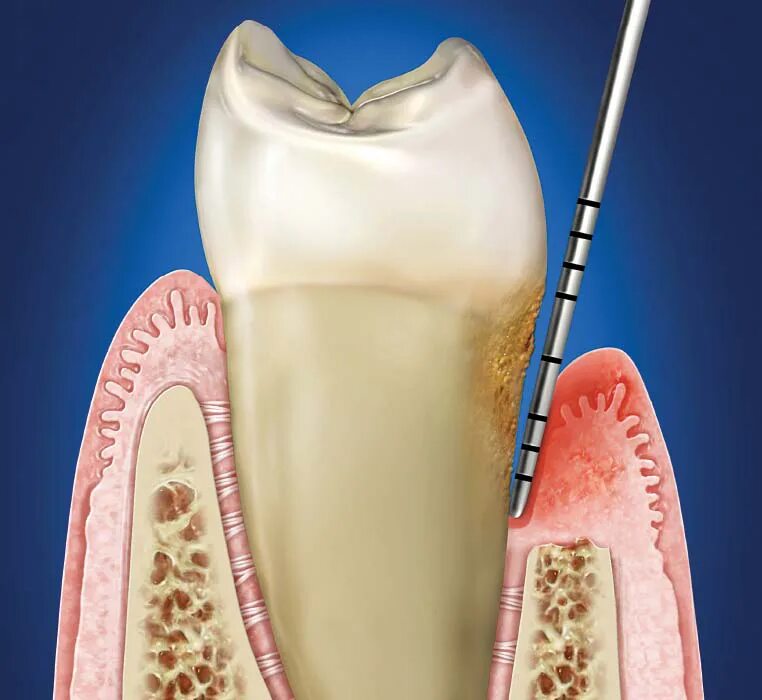

Зубной карман